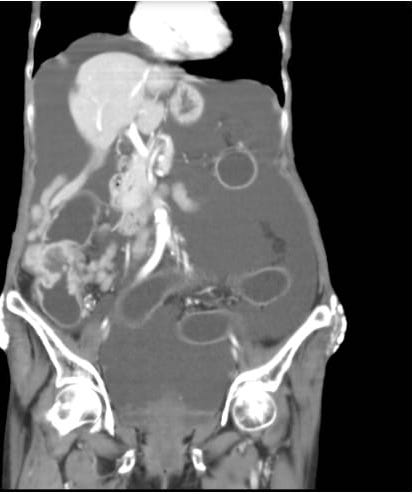

Patient was apparently asymptomatic 2 months back and then developed abdominal pain which was insidious in onset gradually progressive in the epigastric and left hypochondrium region.It was dragging type of pain aggravated on eating food and relieved on taking medications( medication as suggested by the RMP). The patient developed abdominal distension 10 days back. On 2 weeks back, she was taken to the _______ hospital for treatment of pain where an x ray was taken and was referred to ____ _______as a mass was found in the intestines( no documentation found with the patient and thier attenders) she was admitted to the AMC on same day. The patient has no history of vomitings, loose motions, constipation,burning micturition, and decreased urinary output.